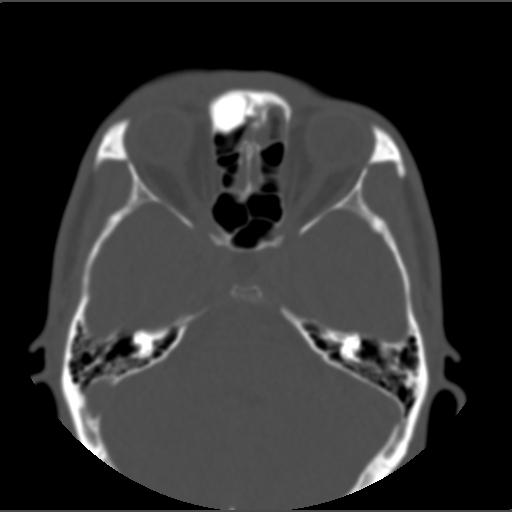

m49y外伤常规ct发现筛额窦右侧高密度块影 。

右侧额筛都内致密性高密度影,余骨皮质未见明显异常改变,右额皮下血肿伴少许积气,我想是致密影是骨瘤.

右侧额筛都内致密性高密度影,境界清楚,余骨皮质未见明显异常改变,符合骨瘤表现

右侧额筛都内致密性高密度影,境界清楚,余骨皮质未见明显异常改变,考虑额筛窦内生性骨瘤.

颅面部骨瘤一般密度致密,多发额骨及鼻窦腔壁,呈扁丘样改变.边界清楚,大部分密度均一.

1、致密型骨瘤。2、右额部头皮挫裂伤。

右额窦至密性骨瘤,右额骨皮下软组织挫伤拌积气.